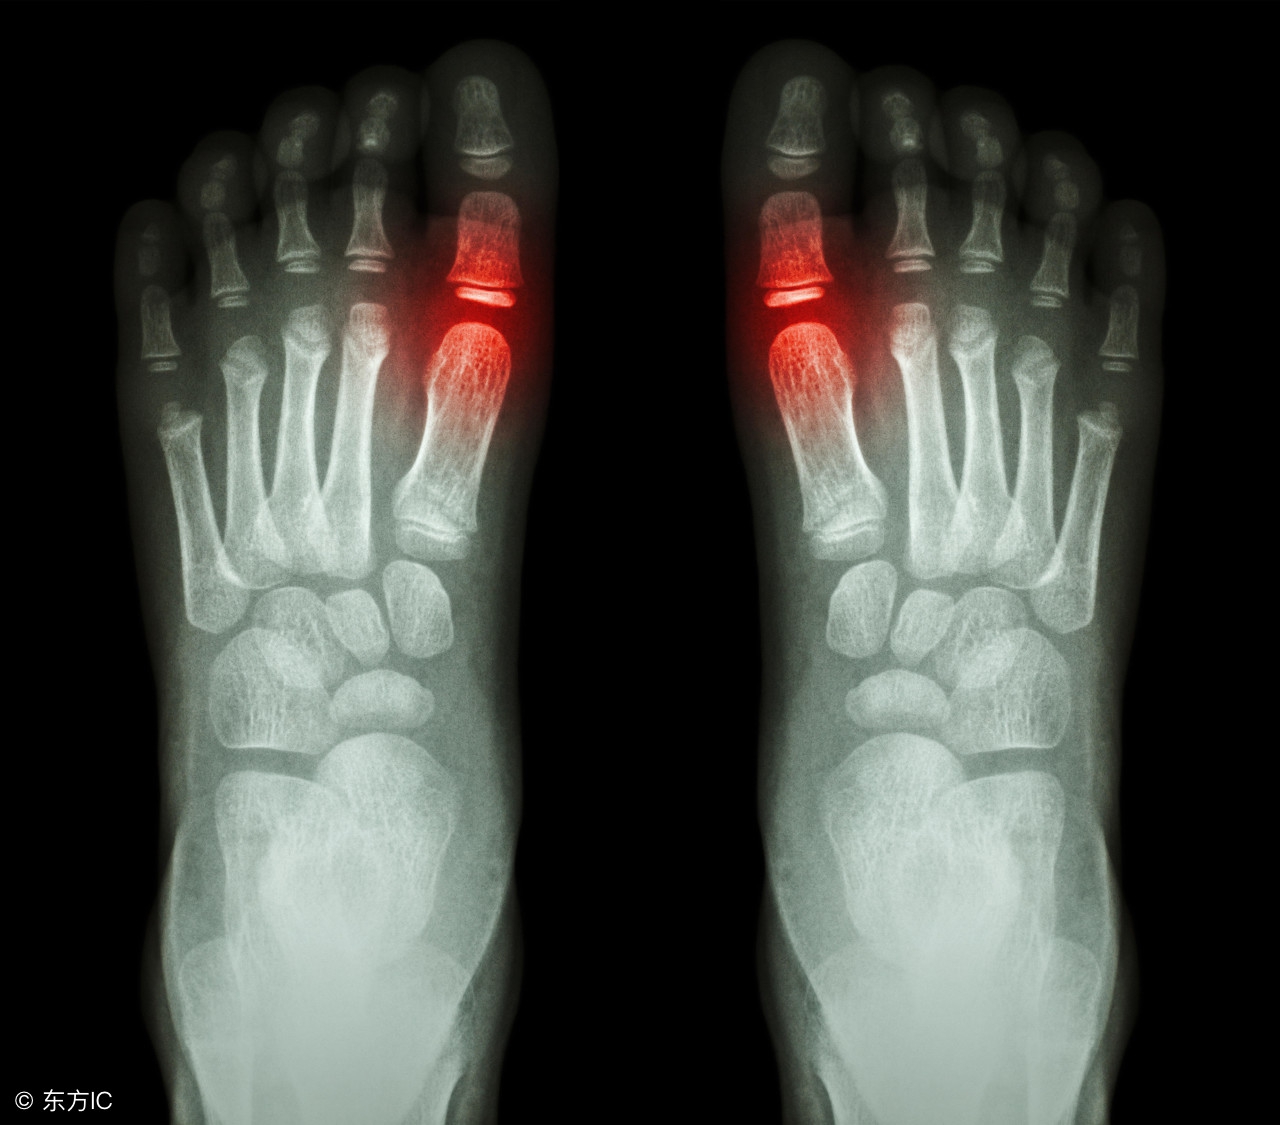

得了痛风之后,止痛、降尿酸、碱化尿液是治疗三部曲。而作为三部曲中最重要的一环降尿酸,目前常用的方法有两种:一种是通过减少体内尿酸的生成量,一种是增加尿酸的排泄量。

尿酸是体内嘌呤代谢后的产物,主要随尿液排出体外。若因长期吃大量高嘌呤食物或其他原因,导致尿酸产生量增加,超出尿酸排泄量,就会使尿酸在体内蓄积。